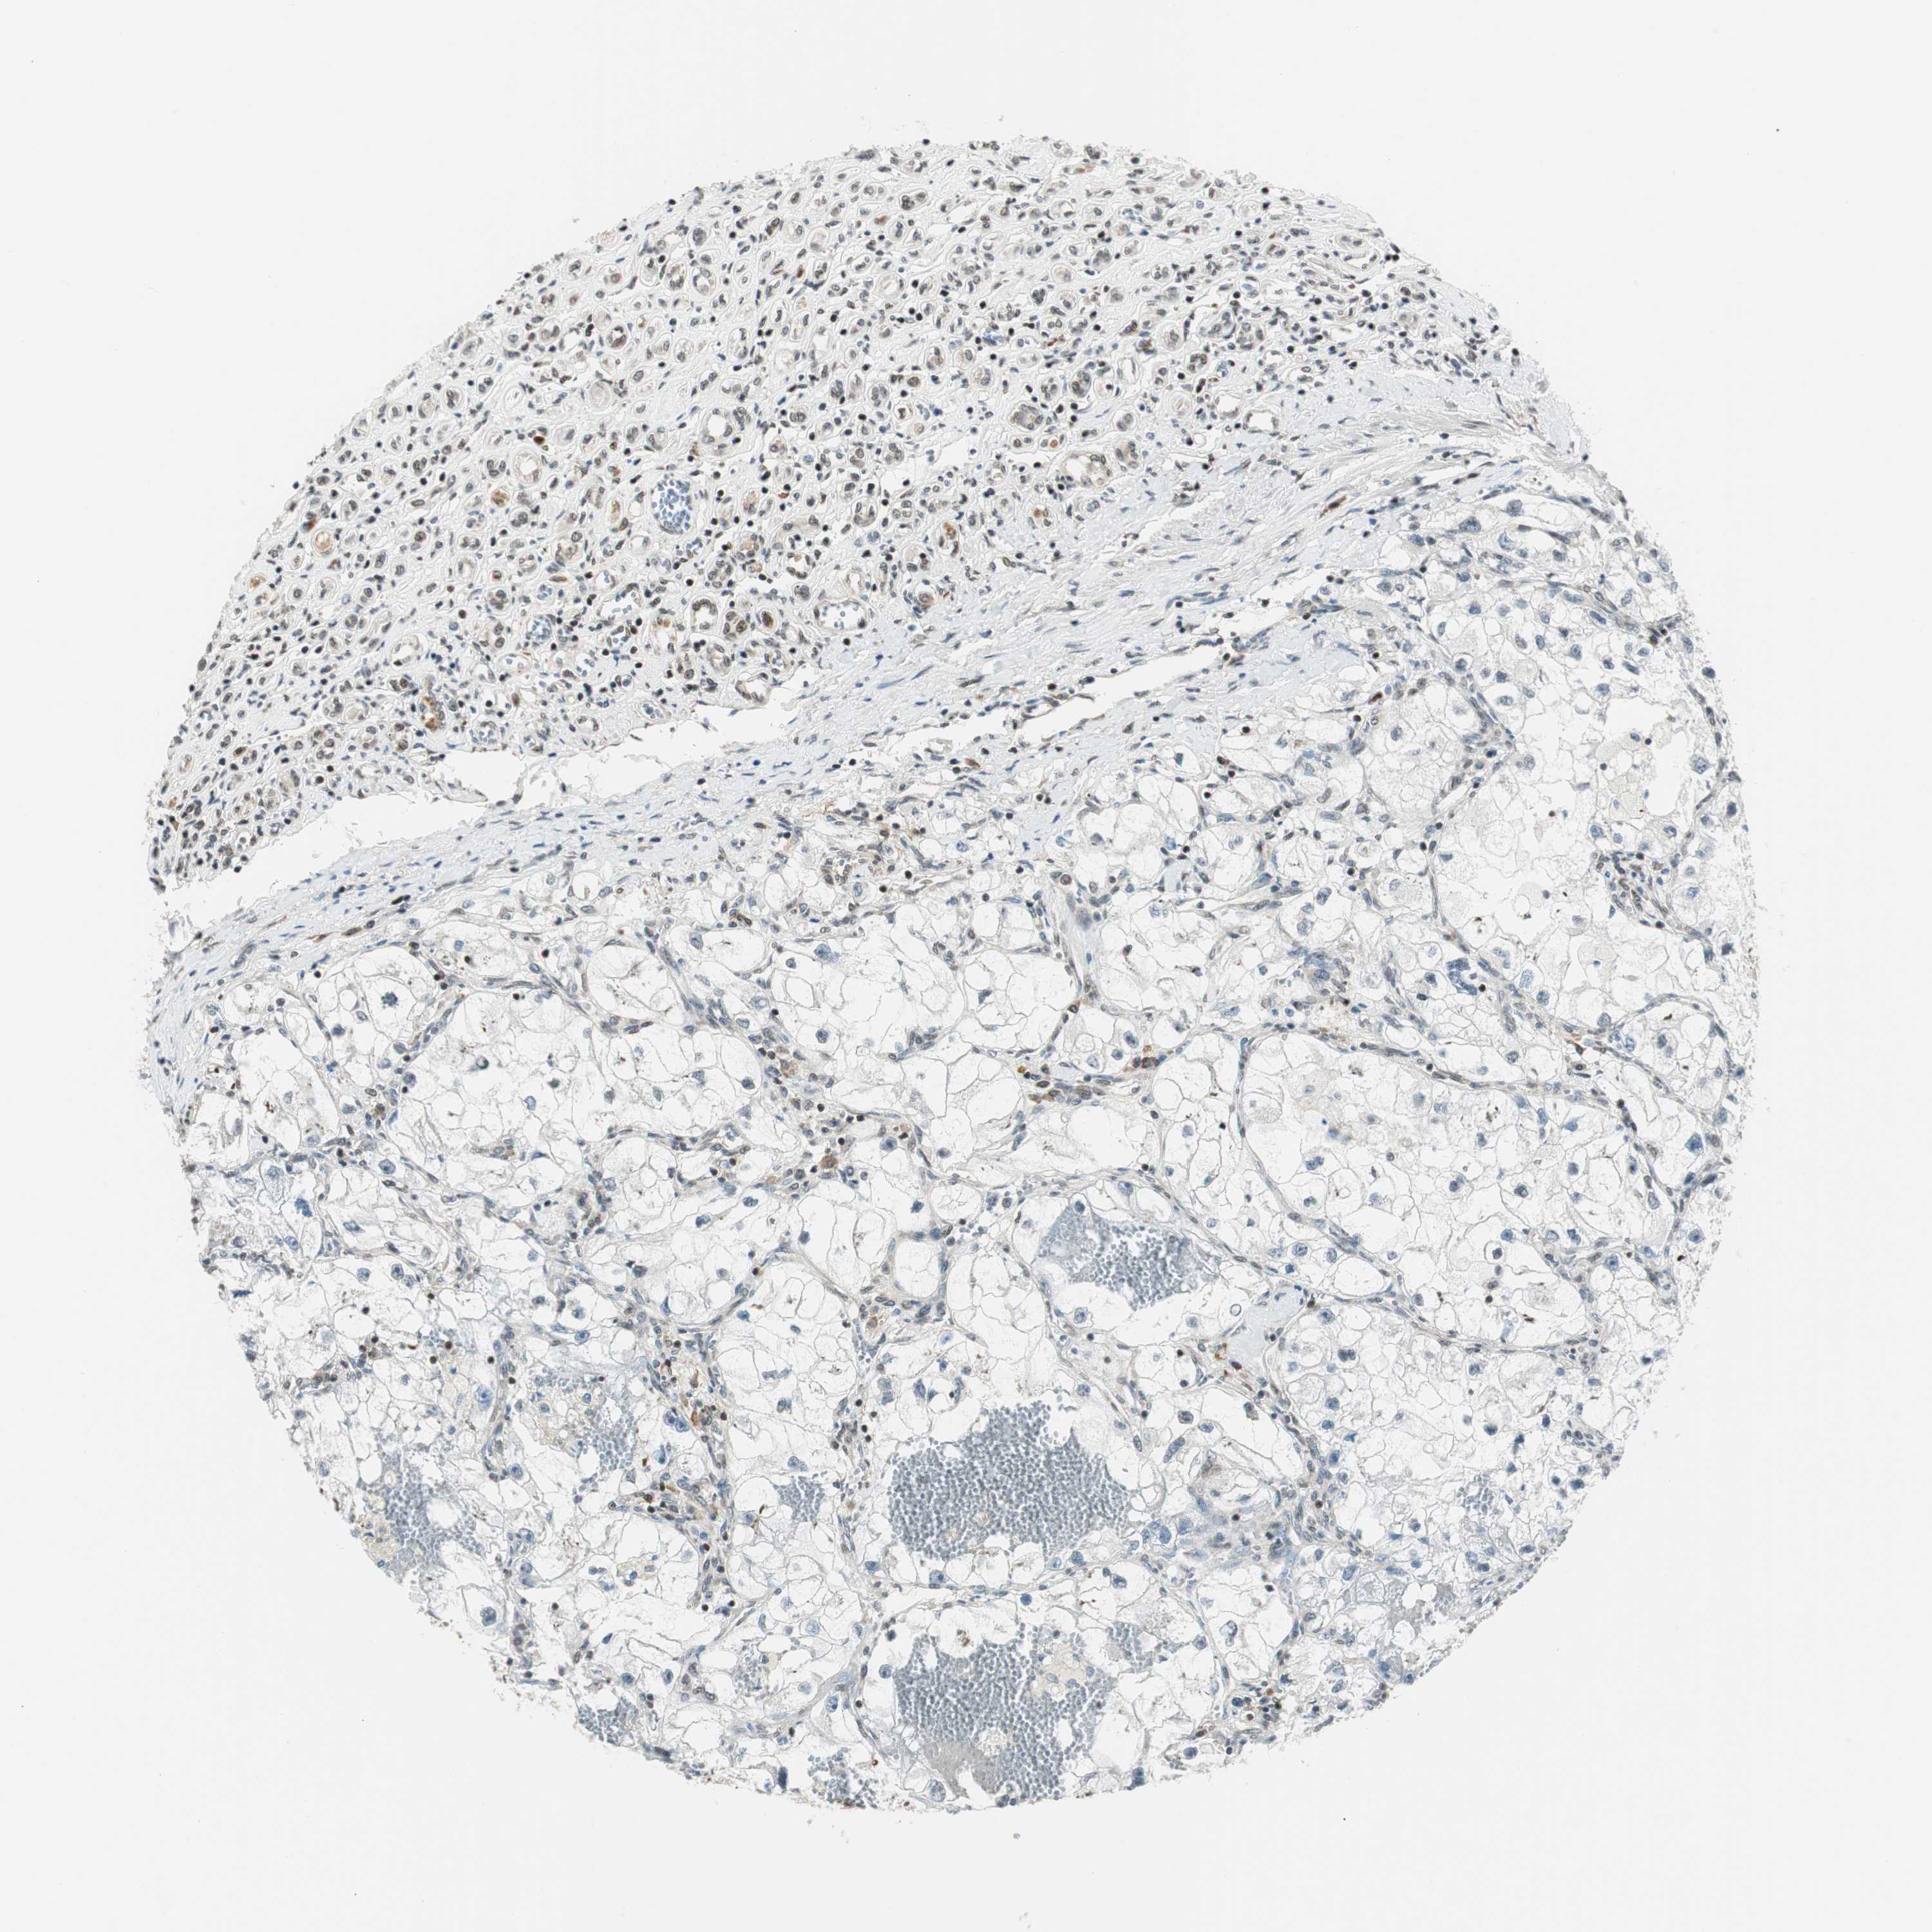

KIDNEY RENAL CLEAR CELL CARCINOMA (VALIDATION) - Interactive survival scatter ploti

The Survival Scatter plot shows the clinical status (i.e. dead or alive) for all individuals in the patient cohort, based on the same data that underlies the corresponding Kaplan-Meier plots. Patients that are alive at last time for follow-up are shown in blue and patients who have died during the study are shown in red.

The x-axis shows the expression levels (FPKM) of the investigated gene in the tumor tissue at the time of diagnosis. The y-axis shows the follow-up time after diagnosis (years). Both axes are complimented with kernel density curves demonstrating the data density over the axes. The top density plot shows the expression levels (FPKM) distribution among dead (red) and alive patients (blue). The right density plot shows the data density of the survived years of dead patients with high and low expression levels respectively, stratified using the cutoff indicated by the vertical dashed line through the Survival Scatter plot. This cutoff is automatically defined based on the FPKM cutoff that minimizes the p-score. The cutoff can be changed by dragging the vertical line or by entering a cutoff value in the square labeled "Current cut-off".

Under the Survival Scatter plot the p-score landscape (black curve; left axis) is shown together with dead median separation (red curve; right axis). Dead median separation is the difference in median mRNA expression between patients who have died with high and low expression, respectively. It is calculated as follows: median FPKM expression of dead patients with high expression - median FPKM expression of dead patients with low expression. This is intended to aid the user in visually exploring custom cutoffs and the associated p-scores and dead median separation.

Individual patient data is displayed and can be filtered by clicking on one or more of the category buttons on the top of the page. Categories describing expression level and patient information include: high, low, alive, dead, female, male and tumor stages. The scale of the x-axis can be toggled between linear and log-scale by clicking on the "x log" button. Mouse-over function shows TCGA ID, patient information and mRNA expression (FPKM) for each patient.

& Survival analysisi

Kaplan-Meier plots summarize results from analysis of correlation between mRNA expression level and patient survival. Patients were divided based on level of expression into one of the two groups "low" (under cut off) or "high" (over cut off). X-axis shows time for survival (years) and y-axis shows the probability of survival, where 1.0 corresponds to 100 percent.

RING1 is not prognostic in Kidney Renal Clear Cell Carcinoma (validation)

Best expression cut offi

Based on the FPKM value of each gene, patients were classified into two groups and association between prognosis (survival) and gene expression (FPKM) was examined. The best expression cut-off refers the FPKM value that yields maximal difference with regard to survival between the two groups at the lowest log-rank P-value. Best expression cut-off was selected based on survival analysis .

When clicking on this number, the vertical dashed line indicating cut-off, the interactive survival plot, and the Kaplan-Meier curve will be adjusted to show results based on the best expression cut-off.

: 28.79

P scorei

Log-rank P value for Kaplan-Meier plot showing results from analysis of correlation between mRNA expression level and patient survival.

N/A

5-year survival highi

5-year survival for patients with higher expression than the expression cutoff.

For melanoma and glioma, 3-year survival is shown.

5-year survival lowi

5-year survival for patients with lower expression than the expression cutoff.

TCGA RNA samplesi

RNA-seq data is reported as average FPKM (number Fragments Per Kilobase of exon per Million reads), generated by the The Cancer Genome Atlas (TCGA) .

Normal distribution across the dataset is visualized with box plots, shown as median and 25th and 75th percentiles. Points are displayed as outliers if they are above or below 1.5 times the interquartile range. FPKM values of the individual samples are presented next to the box plot.

Average pTPM 31.4

Number of samples 100